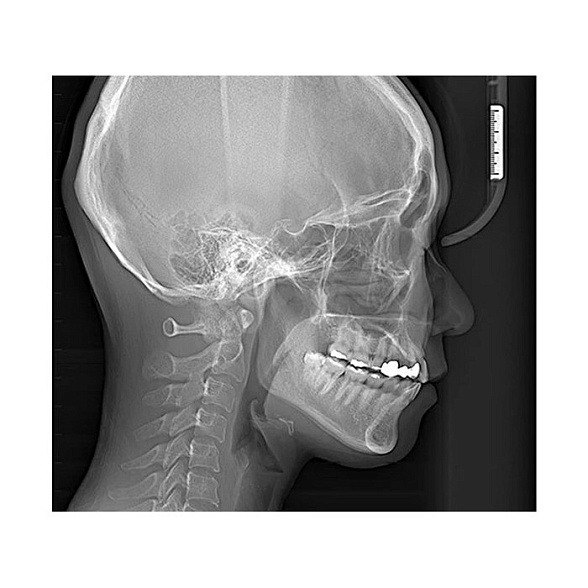

Трехмерные режимы (3D КЛКТ):

- Сканирование одной или обеих челюстей.

- Прицельное сканирование отдельного сегмента (например, области 2-3 зубов для планирования имплантации).

- Исследование ВНЧС с высоким разрешением.

- Сканирование верхнечелюстных пазух.

- Режим сканирования airway (дыхательных путей) для ортодонтической диагностики.

Гибкость настроек Field of View (FOV, поле обзора) позволяет выбрать оптимальный объем сканирования: от небольшого участка для экономии дозы облучения до полного сканирования обеих челюстей для комплексного планирования лечения. Это дает врачу полный контроль над диагностическим процессом.